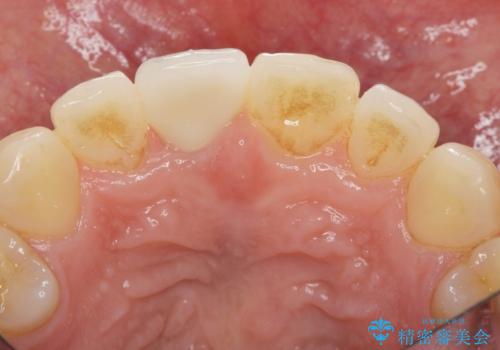

前歯の変色 打撲により失活した前歯の根管・セラミック治療

- 変色してきた前歯の形態回復、色調の改善を求めて来院されました。

X線検査、歯髄(歯の神経)の検査を行ったところ、失活(歯の神経の死んだ状態)であると診断されました。

放置すると変色が進行するだけでなく、根尖病変も形成される恐れが強いことから、根管治療を行ったのちセラミッククラウンによる審美性の改善を計画します。